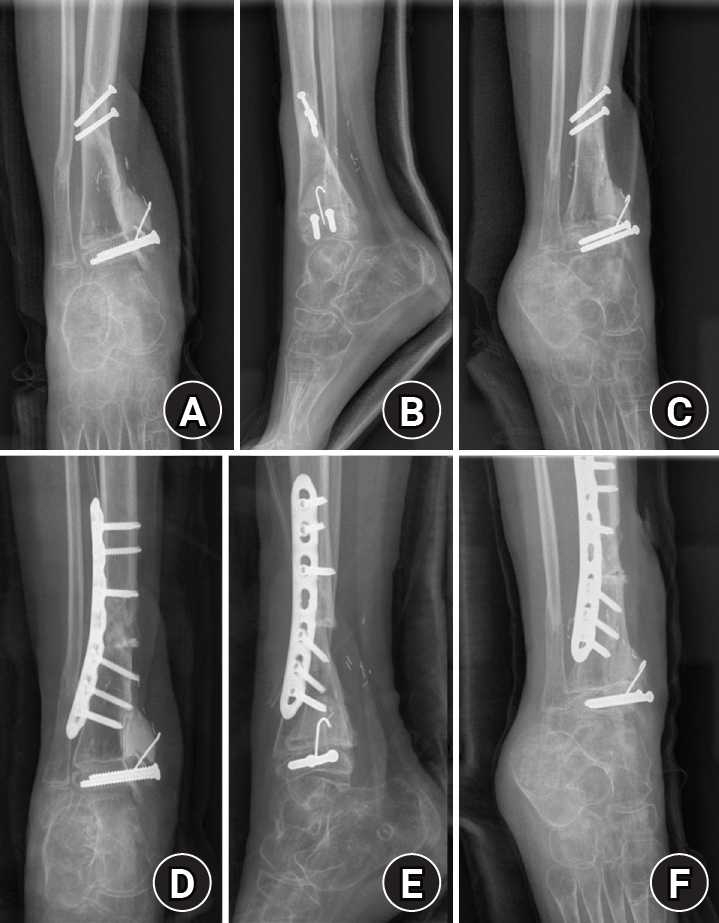

Fig. 6.

Corrective osteotomy for progressive varus deformity. (A) Preoperative anteroposterior radiograph obtained during follow-up, showing progressive varus deformity of the ankle. (B) Preoperative lateral radiograph obtained during follow-up. (C) Preoperative mortise radiograph obtained during follow-up. (D) Postoperative anteroposterior radiograph obtained after corrective osteotomy and plate fixation. (E) Postoperative lateral radiograph obtained after corrective osteotomy and plate fixation. (F) Postoperative mortise radiograph obtained after corrective osteotomy and plate fixation.

Stage 3 (deformity correction; January 9, 2017)

Progressive varus deformity during follow-up was treated with corrective osteotomy and plate fixation (Fig. 6).

Stage 4 (alignment and contracture management; May 29, 2017)

The patient was observed for more than 6 months after plate fixation, and bone union was achieved for the remaining fracture sites. However, varus deformity gradually occurred (lateral distal tibial angle, 111.5º; tibiotalar tilt, 0.4º). As the patient was relatively young and had substantial remaining growth, early correction was considered advantageous and was therefore performed. Residual deformity tendency and contracture were managed with additional procedures including Achilles tendon lengthening and Z-plasty for tendon/skin contracture release. The bone-cement spacer was removed during this phase. Alignment correction/overcorrection and continued alignment management were supported with an Ilizarov external fixator (Fig. 7). After applying the Ilizarov external fixator for 3 months, radiologic indices were corrected (lateral distal tibial angle, 97.6º; tibiotalar tilt, 0.3º).